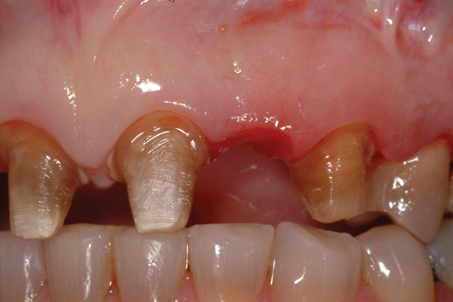

(10.) Close-up view of the existing edentulous tooth No. 10 site prior to the creation of the ovate pontic site.

Figure 10